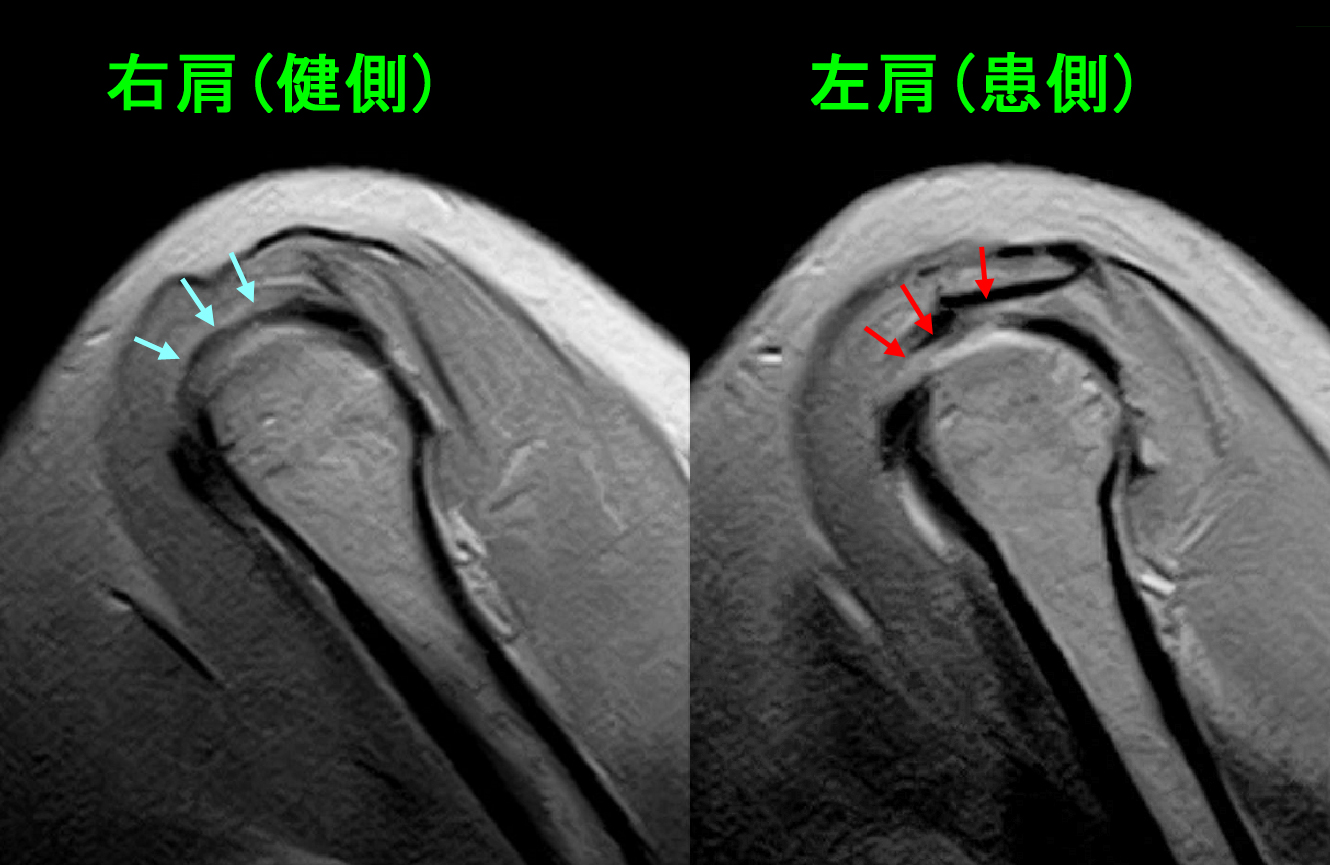

MRIの検査からは、五十肩発症の要因は良くみられる棘上筋腱の炎症であることが推察されました。

MRI画像で、赤矢印の部分(骨の上にのっている黒い腱が白っぽくなっているの)が棘上筋腱の炎症所見です。